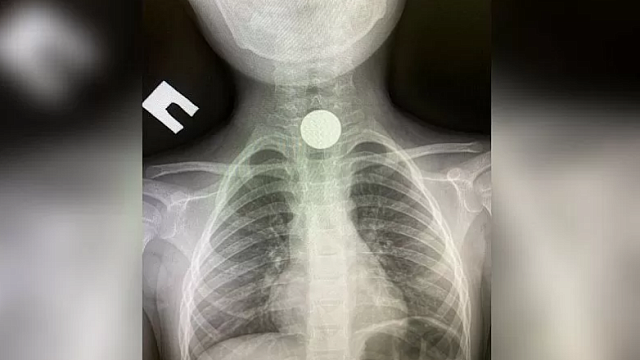

В Туапсе в районную больницу 28 февраля поступил 4-летний пациент. Врачи провели исследование и обнаружили в желудочно-кишечном тракте ребенка монету. Об этом случае в своем аккаунте в Instagram рассказал врач Гор Саакян.

«Была проведена рентгенография с подтверждением диагноза инородного тела (монета). Была проведена лечебная гастроскопия под ЭТН ( эндотрахеальный наркоз), с целью эвакуации инородного тела без оперативного вмешательства», - рассказал Гор Саакян.

Врач уточнил, что процедура прошла успешно.